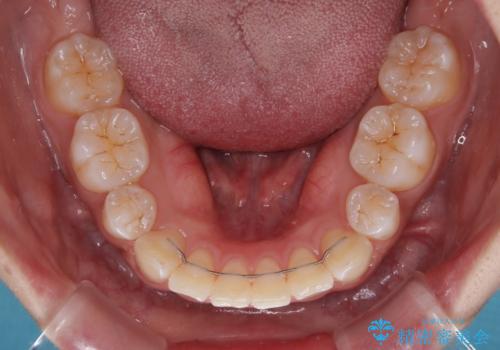

強い咬合力により前歯の隙間がなかなか閉じられず、治療期間は長いものとなりましたが、横顔の印象が大きく変わるほど口元の印象を改善することができました。

- 矯正治療後の保定が不十分だと後戻り(元の位置に戻ろうとする動き)をします